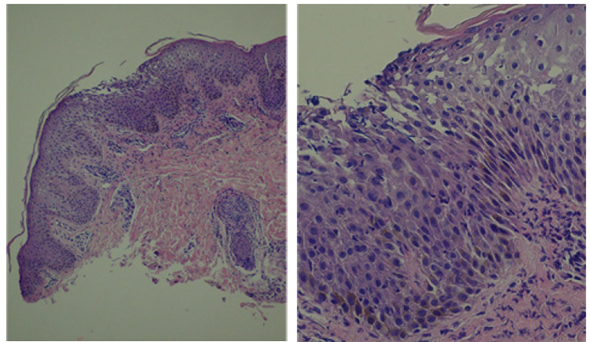

Debido a la extensión de las lesiones, se decidió el ingreso a una sala de cuidados moderados, para realizar un abordaje y seguimiento interdisciplinario guiado por pediatra y dermatólogo. La anatomía patológica reveló una dermatitis pustular subcorneal formada por acúmulo de neutrófilos (pústulas espongiformes de Kogoj) y vasos tortuosos en la dermis con exudado inflamatorio perivascular, confirmando la sospecha clínica de PPG (Figura 2).

Figura 2 Microscopía óptica de las lesiones. Tinción hematoxilina-eosina, (A) x10; (B) x40. Pústula subcorneal, techo estrato córneo roto, cuerpo mucoso. Leve hiperplasia y espongiosis. Vasos tortuosos en la dermis con infiltrado inflamatorio perivascular.

Junto a la presentación clínica característica, el estudio histopatológico contribuye a descartar diferenciales10. La anatomía patológica informó la presencia de lesiones pustulosas con leucocitos polimorfonucleares neutrófilos adyacentes al estrato córneo en acúmulos característicos de la PGG2. También puede observarse paraqueratosis, acantosis, hiperqueratosis, disminución del grosor del estrato granuloso, edema y dilatación de los capilares de la dermis11. En este caso, dados los hallazgos anatomopatológicos característicos y la evolución clínica, no se realizó la técnica de inmunofluorescencia directa para descartar o confirmar otros diagnósticos diferenciales como el pénfigo IgA.